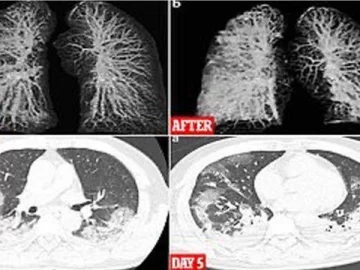

Los especialistas del Instituto Nacional de Enfermedades Infecciosas en Roma estudiaron los cuerpos de los pacientes de 65 y 67 años y detectaron, mediante rayos-X y tomografías computarizadas, un gran deterioro en la función de los pulmones.

Cuando coronavirus ataca los pulmones, provoca una inflamación en las membranas mucosas, lo genera un daño en los alvéolos pulmonares, que tienen que trabajar más para suministrar oxígeno a la sangre que circula por todo el cuerpo y eliminar el dióxido de carbono para que se pueda exhalar. La inflamación y el daño al flujo de oxígeno pueden causar que dichas áreas en los pulmones se llenen de fluido, pus y células muertas.